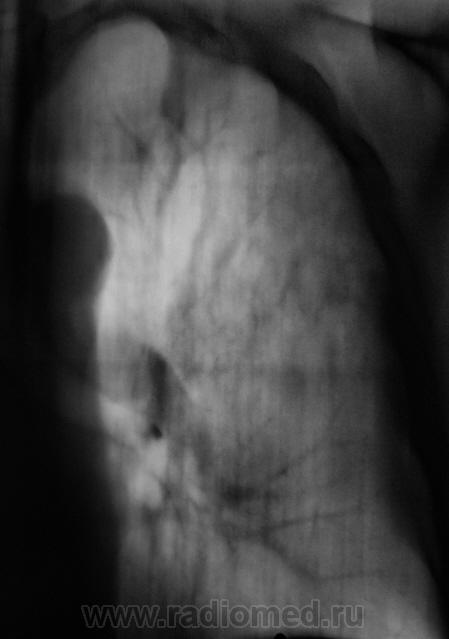

При расшифровке флюорограмм пациент "взят на контроль". Жалоб пациент не предъявляет. Подняли "архив", флюорограмма за 2009 г. - "норма".

Произвели стандартное дообследование.

Томограммы.